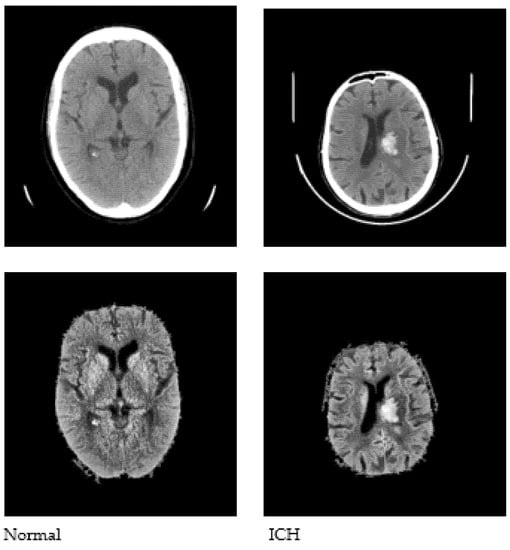

Pre-processing is performed as a fundamental step to enhance the quality of the input images, which aids in the subsequent stages of image analysis. Pre-processing facilitates the removal of noise, unwanted areas in the input images (such as the skull and scalp), and the extraction of the intracranial region of the brain in the image. Contrast Limited Adaptive Histogram Equalization (CLAHE) [28] is used, followed by Otsu’s thresholding [29], in order to obtain binarized image data. The largest connected component is selected as the skull mask, and the region of interest (ROI) is extracted by masking the enhanced images. Sample images after pre-processing are shown in Figure 3.

Figure 3.

Sample CT images after pre-processing.